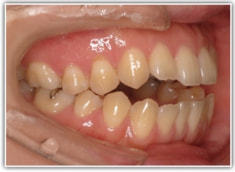

治療前

かなり重度のオープンバイト症例です。骨格的な要素も強く出ております。通常であれば外科矯正適応のパターンですが、当院では矯正治療のみで、外科は行いません。